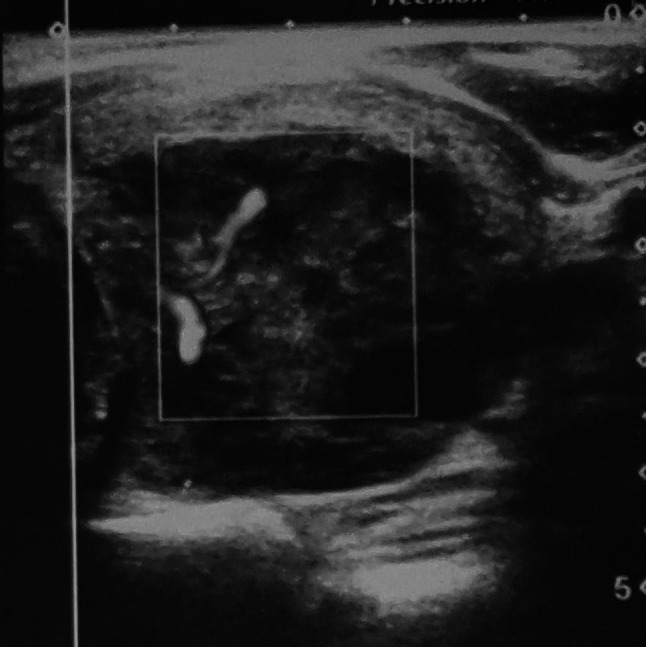

A 43 years old man presented to ENT outpatient department with a history of anterior neck swelling for 2 weeks. There was no history of exposure to neck radiation. Other medical and family history was not significant. On examination, there was enlarged left lobe of the thyroid gland. Thyroid function tests were within normal limits. Ultrasonography (USG) of neck showed hyperechoic lesion in left lobe of thyroid (42 × 35 mm) with increased vascularity, suggestive of malignant lesion (Fig. 1). Patient was advised for USG guided fine needle aspiration cytology (FNAC) from thyroid swelling. FNA smear showed atypical lymphoid cells with high N:C ratio, irregular nuclear membrane, prominent nucleoli and scant amount of cytoplasm suggestive of Non-Hodgkin’s lymphoma in a background of Hashimoto’s thyroiditis (Fig. 2). Biopsy and immunohistochemistry were advised for confirmation and typing. Patient underwent left hemithyroidectomy and specimen was sent for histopathological examination. Microscopic pictures showed diffuse infiltration by monotonous population of atypical lymphoid cells in focal area (Fig. 3). Individual tumor cells were small to intermediate size, round shaped with scant to moderate amount of cytoplasm and round to oval hyperchromatic nuclei with coarse chromatin pattern and prominent nucleoli. Focal areas of necrosis and hemorrhage were noted. Surrounding thyroid parenchyma showed features of Hashimoto’s thyroiditis. Histopathological diagnosis of Non-Hodgkin’s lymphoma in the background of Hashimoto thyroiditis was given. On immunohistochemistry (IHC), the tumor cells were positive for CD20, CD 45, BCL 2 and PAX 5. Final diagnosis of diffuse large B-cell lymphoma (DLBCL) was made based on these findings. Imaging of chest, abdomen and pelvis and bone marrow aspiration was done to exclude other neoplastic foci. According to the Ann Arbor guidelines for primary thyroid lymphoma, the patient had stage IE disease at diagnosis (Confined to the thyroid gland only). Patient underwent 6 cycles of chemotherapy with R-CHOP (rituximab- cyclophosphamide-doxorubicin-vincristine-prednisone). Patient is now on regular follow up and disease free.

Fig. 1.

Ultrasound scan of left thyroid showing hyperechoic lesion with increased vascularity